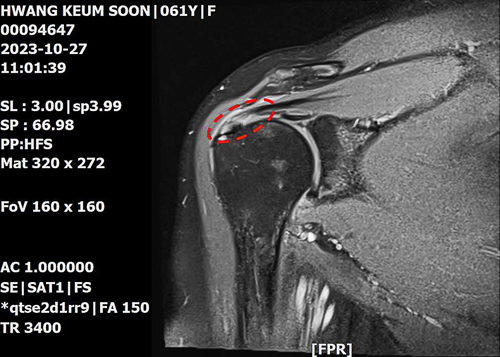

Senior Deaconess Geumsun Hwang | 63, Parish 20 in Manmin Central Church

In October 2023, I went to the hospital due to persistent pain in my right shoulder. A year ago, I tried to pick up a cell phone that fell from the bed and dislocated my right shoulder. At that time, the X-ray results showed no problem, and I only received injections to alleviate the pain.

But the pain got worse and I could not move my arm properly. I went to the hospital for MRI and the result showed tendon rupture in my right shoulder and frozen shoulder. I was scheduled to have surgery in late December. But I decided not to have it because I believed God would be able to heal me.

Rotator cuff tear